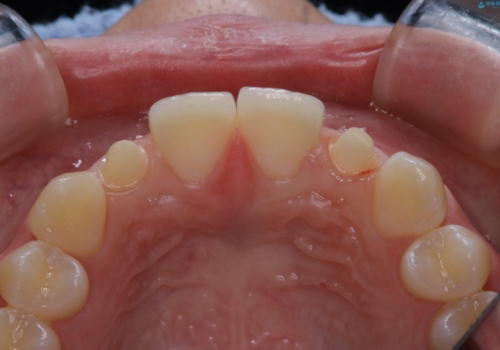

- 初診時、前歯部の見た目の改善を主訴にご来院されました。生まれつき歯が小さい状態の「矮小歯」とそれに伴う正中の「すきっ歯」があるため、大きなガタつきはないものの笑った時の印象に違和感が出る状態となっていました。

矮小歯が傾斜していることなどを踏まえ、より安全に治療を進めるために部分矯正を併用したセラミッククラウンでの治療を行うこととなりました。